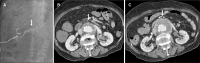

Arterioureteral fistula is a rare but life-threatening condition. An endovascular treatment approach is commonly used; however, there is a potential risk of infection. We present a case in which a patient presented with abdominal pain and was diagnosed with a ruptured internal iliac artery aneurysm and a subsequent arterioureteral fistula. An aortic stent graft was inserted to treat the arterioureteral fistula, but it subsequently became infected, resulting in the patient's death. This case underscores the importance of early diagnosis and treatment of arterioureteral fistula and the possibility of graft infection.